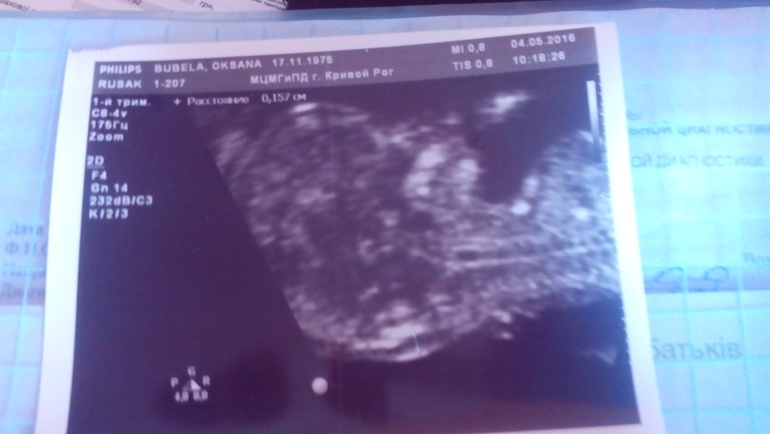

Да,уже человечек,бракался,уворачивался,не давал посчитать сердцебиение))) как ты? Простуда полностью прошла?

Да,сказали предположительно мальчик...Я делала скрининг в генетическом центре,один из лучших у нас в стране,и врачи там квалифицированные.